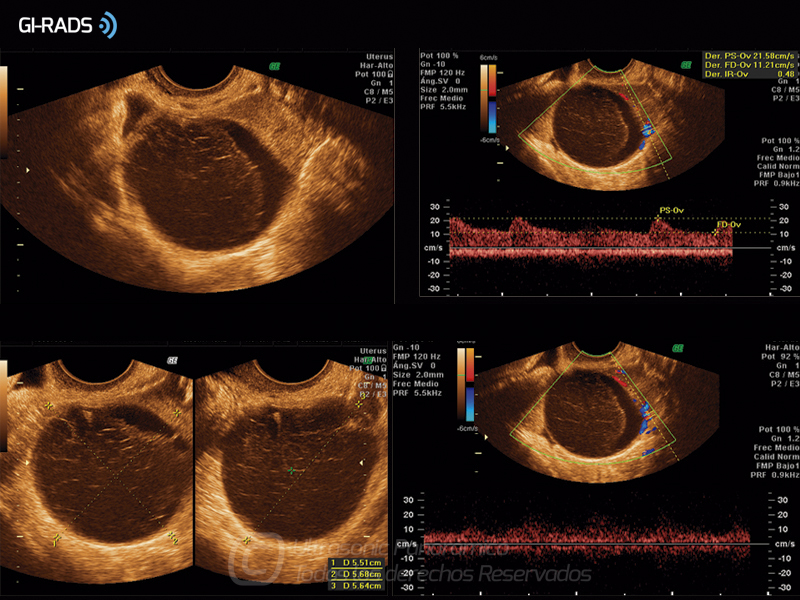

Patologías Benignas – Cuerpo Lúteo Hemorrágico

• Patologías Benignas – Cuerpo Lúteo Hemorrágico